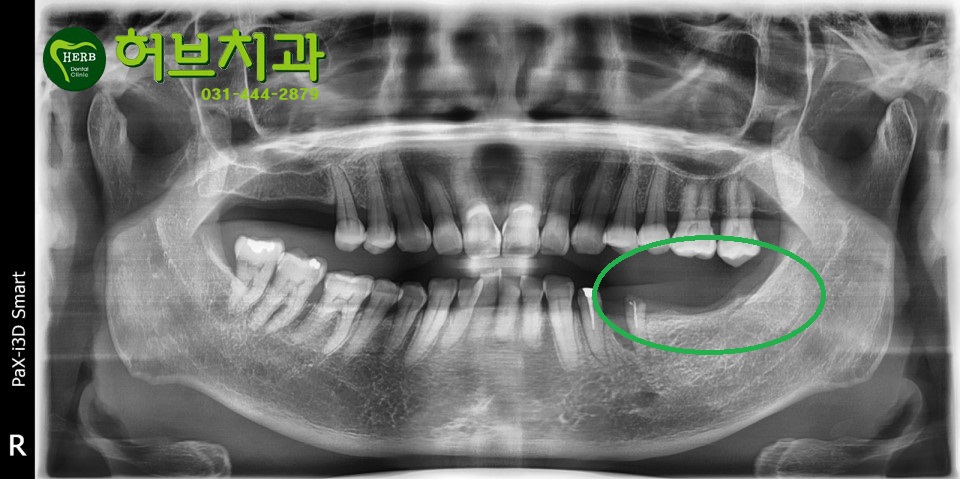

어금니가 양쪽 다 빠지셔서 좌측은 예전에 임플란트가 일상화 되기 전에

칸틸레버 브릿지 즉 작은 어금니를 깎아서 갈아서 씌우고

어금니 뿌리는 없지만

치아를 어금니 모양으로 만들어 작은 어금니에 이어붙여

머리 모양만 만들어 주는 방식으로 치료하는 방법입니다.

예전에 임플란트가 비싸고 일반화 되지 않았을때 많이 사용하던 방법인데

이경우 작은 어금니가 힘을 많이 받아 작은 어금니가 윗분처럼 완전 부러져 버리면서

그쪽 부위 어금니들이 네개 다 무너져 버리는 결과가 발생했습니다.